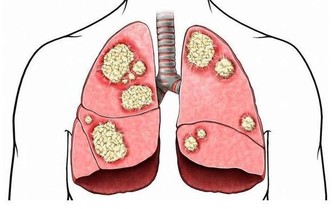

萬古黴素是抗感染的老藥了,臨床上已經使用了50多年,相對來說比較成熟與安全,這種藥物主要用於針對的是革蘭氏陽性球菌感染,尤其對金黃色葡萄球菌有很好的作用。

但這類藥物,仍然有可能引發肝損傷、腎損傷,或是一些過敏樣症狀。例如萬古黴素如果注射過快,患者便容易出現全身性的過敏反應,稱作紅人綜合徵,因此使用此類藥物時,盡量應在醫生在場的情況下使用。